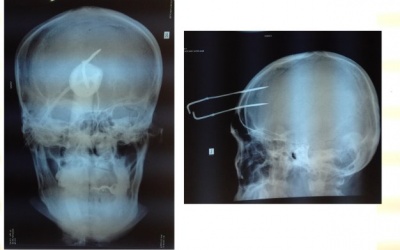

Bé Lê Thanh H. (3 tháng tuổi, ở xã An Thạnh Thủy, huyện Chợ Gạo, Tiền Giang) được mẹ đưa vào Bệnh viện Đa khoa tỉnh sáng 12/9 vì bị té võng.